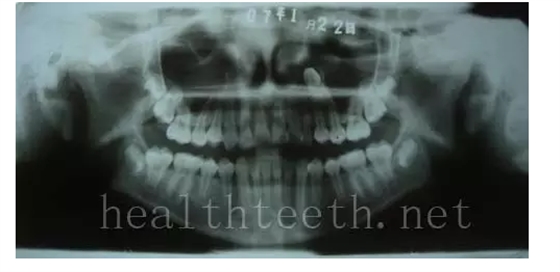

病例2

QQ圖片20150722094347.png

QQ圖片20150722094402.png

病例3,同時多生兩顆牙齒

QQ圖片20150722094417.png